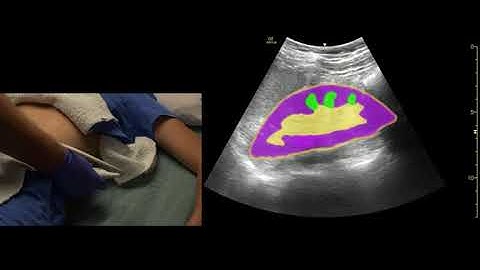

#howto measure the kidney in diSplay U/S simulator